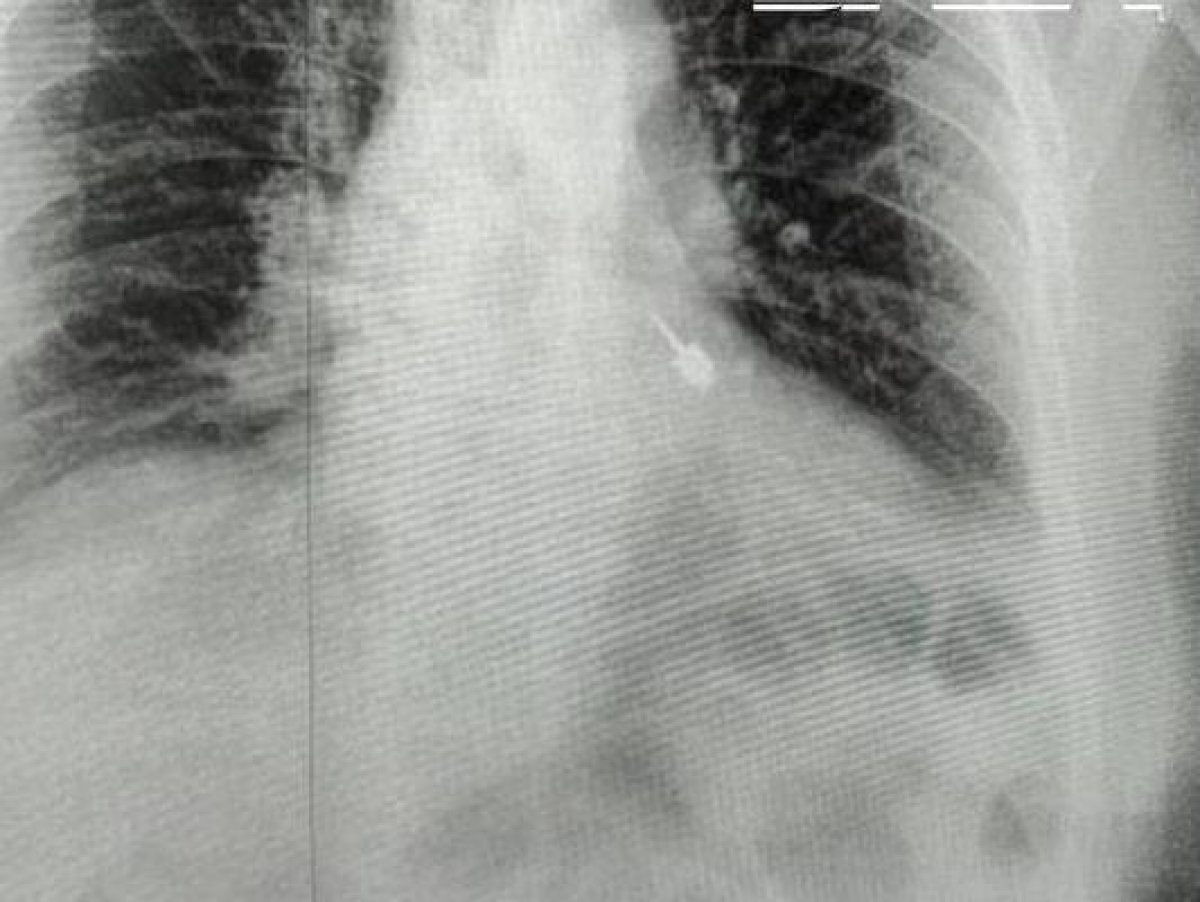

Пациент сразу почувствовал резкую боль и обратился за помощью в больницу. Обследование с помощью рентгена показало, что инородный предмет находится в левом бронхе. Ситуация потребовала экстренного вмешательства. Врачи приняли решение о срочной операции, поскольку нахождение металлического предмета в дыхательных путях могло привести к серьезным осложнениям, включая повреждение тканей, развитие инфекции и угрозу для жизни.

Медицинская команда Мытищинская больница выполнила сложную эндоскопическую процедуру по извлечению инородного тела. По словам специалистов, операция требовала высокой точности: острые края инструмента могли повредить стенки бронха и вызвать внутреннее кровотечение. С помощью эндоскопического оборудования врачи аккуратно зафиксировали бур и извлекли его без повреждения дыхательных путей. Благодаря слаженной работе медиков удалось избежать осложнений, и состояние пациента стабилизировалось.